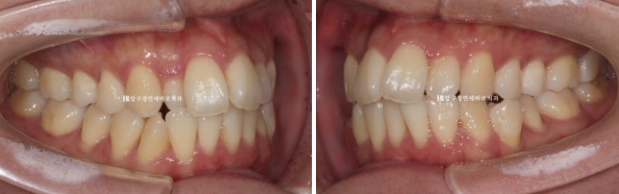

측절치 덧니가 아랫니와 거꾸로 물리는 반대교합을 보입니다.

반대쪽 파란 화살표 부분 작은 어금니 역시 배열에서 튀어나가 있어서 윗니와 거꾸로 물리는 반대교합입니다.

거꾸로 물리는 덧니는 해결이 되었고

24.02~24.08

작은 어금니까지 배열을 마쳤습니다.